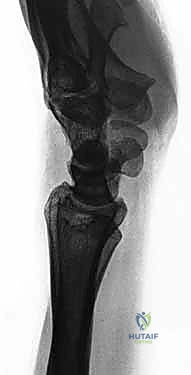

On plain radiographs, we look for five characteristic findings:

* Terry Thomas sign: A scapholunate gap exceeding 3 mm on a PA radiograph.

* Cortical ring sign: Hyperdensity of the scaphoid cortex on PA view due to increased scaphoid flexion.

* Angular changes:

* Scapholunate angle: Normal is 30-60 degrees; >60 degrees suggests SLIL injury.

* Capitolunate angle: Normal is ±15 degrees; >15 degrees suggests SLIL injury.

* Radiolunate angle: Normal is ±10 degrees; >10 degrees suggests SLIL injury.

* Quadrangular lunate: The lunate appears rectangular on PA view as it moves into extension.

* Disruption of Gilula’s lines: The smooth, concentric arcs outlining the carpal rows are interrupted.